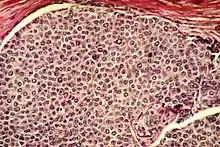

Carcinoma

Carcinoma Leukaemia

- Carcinoma, the majority of cancer cells are epithelial in origin, beginning in a tissue that lines the inner or outer surfaces of the body.